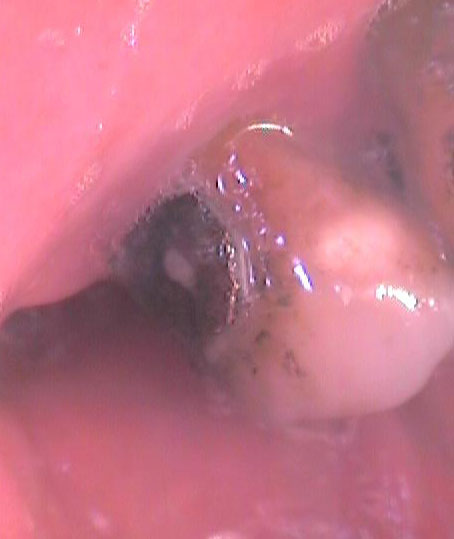

Трети случай